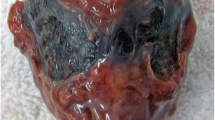

The accumulation of HGA in blood is central to the pathophysiology of the disease. It is proposed that HGA is oxidised to 1,4-benzoquinone-2-acetic acid (BQA) (Zannoni et al 1969). It is thought that BQA polymerises to form a melanin like pigment, which deposits in connective tissues in a process called ochronosis. The consequences of this chronic process are typically observed from the third to fourth decade of life and include spondyloarthropathy, rupture of ligaments/muscle/tendons, valvular heart disease including aortic stenosis and renal and prostate stones (Ranganath et al 2013). Acute metabolic decompensation can occur in AKU presenting with fatal complications, including oxidative haemolysis and or methaemoglobinaemia. It is the latter that will form the basis of this article. Herein the pathophysiology of why these acute complications may occur and the current literature will be reviewed.

HGA undergoes auto-oxidation to form BQA polymers, also referred to as ‘soluble melanins’ (Hegedus and Nayak 1994). The latter are purported to have pro-oxidant properties. It is proposed that the oxidative stress associated with these melanins and their associated metabolites/free radicals (i.e. of oxygen radicals such as superoxide anion, hydroxyl radical and hydrogen peroxide) are a potential ‘trigger’ for oxidative haemolysis. Adding vitamin C and glutathione to cultured cells has been shown to reverse oxidative haemolysis (Hegedus and Nayak 1994).

The role of oxidative stress and its contribution to the mechanisms of the ochronotic process have been studied extensively. This is a progressive chronic disorder and thus an extensive discussion is beyond the scope of this article that is concerned with the acute metabolic complications that can be observed in AKU (see Braconi et al 2015 for a recent review).